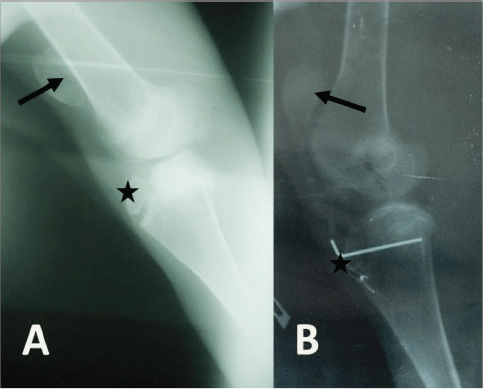

Radiographically, the stifle areas of the affected goats showed ventrocaudal PL in three cases (Figs. 2 and 3) and dorsal PL in the other two cases, for which surgical treatment was performed (Fig. 4A).

Fig. 2. Mediolateral radiograph of the right stifle of a 12-month-old goat with a unilateral PL. The radiograph shows a severely ventrocaudally luxated patella (black arrow) with loss of trabecular pattern of the distal extremity of femur (star), probably due to trochlear ridge hypoplasia. The infra-patellar fat bad is superimposed by a joint fluid due to stifle joint effusion (white arrow).

Fig. 3. Mediolateral radiograph of the right (A) and left (B) stifle of a 3-month-old goat with bilateral PLs. The radiograph shows severely ventrocaudally luxated patellae (arrows).